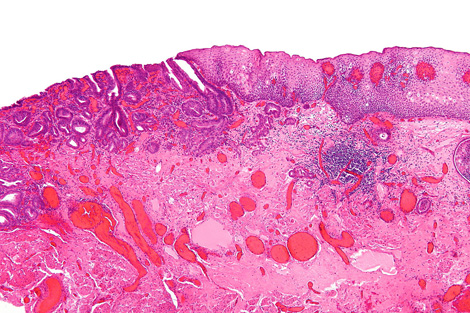

A team led by biophysicist Peter Weightman uses the ALICE accelerator at England’s Daresbury Lab to image the biochemical composition of tissue from patients afflicted by a condition called Barrett’s esophagus. Barrett’s sufferers are 10 times more likely to develop esophageal cancer, but most acquire symptoms too late for treatment.

With ALICE-created images, doctors can distinguish pre-cancerous tissues from benign ones. The method may one day give diagnoses in time to save lives.

Doctors currently diagnose pre-cancerous tissues in patients with Barrett’s esophagus by analyzing random cell samples. This technique can miss areas with telltale changes, says University of Liverpool gastroenterologist Mark Pritchard, who works on Weightman’s team. If the new technology is shown to be accurate and reliable, it could give doctors a more comprehensive view.

To measure cancer cues, scientists tune the ALICE accelerator’s infrared light to a wavelength that excites one specific type of cellular component, such as DNA or proteins. When the light shines into the sample, the excited electrons from that component lose their energy in the form of photons—light researchers can see. They collect this reflected light with a micron-wide tube that they spend about an hour scanning slowly over the entire tissue surface. The result is a map of the density of one component, such as DNA, across the sample.

For each sample, the researchers repeat the process to map three or four different components known to vary in cancerous versus noncancerous tissues. “When you go cancerous, the DNA goes up and the protein goes down,” Weightman says. That’s because cancer cells have more active DNA than healthy ones, facilitating the cell growth and DNA duplication necessary for a tumor to form.